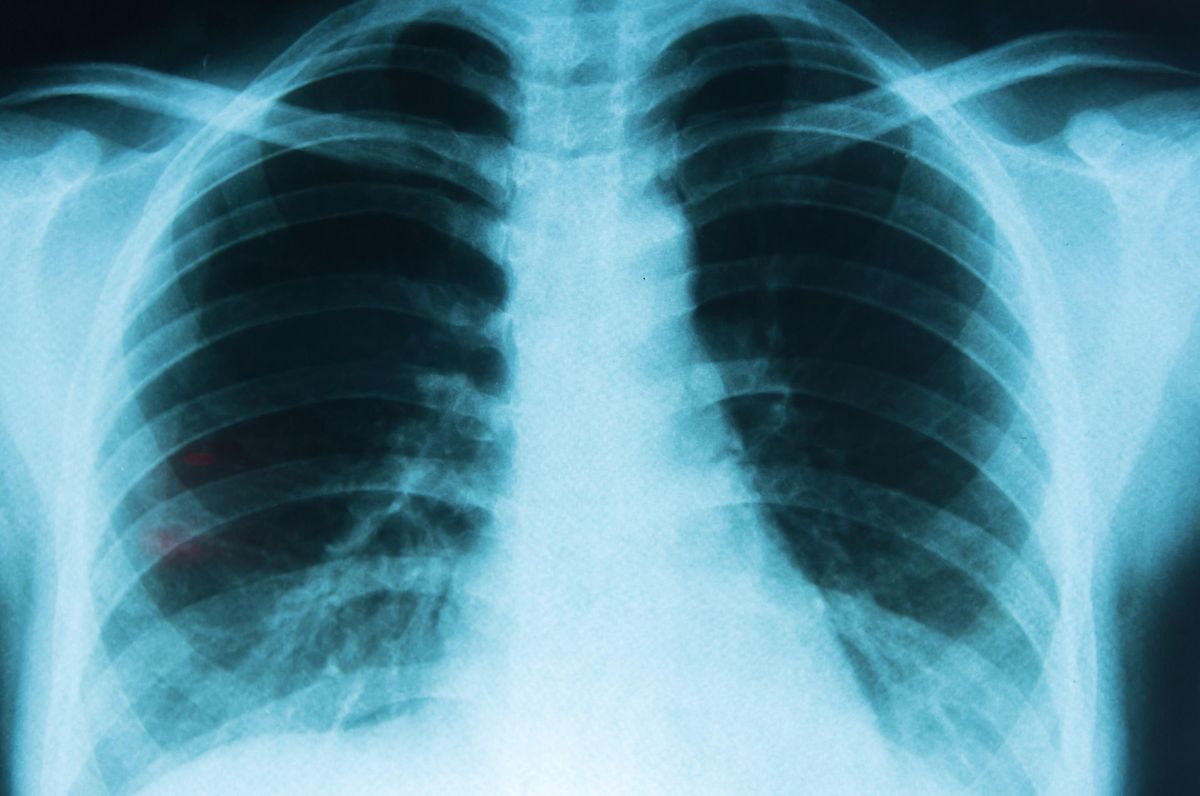

Preocupación por alta tasa de cáncer de pulmón en Antofagasta

Expertos alertan sobre la alarmante diferencia epidemiológica en la incidencia de cáncer de pulmón en Antofagasta, que es 7 a 8 veces mayor que en otras regiones del mundo.